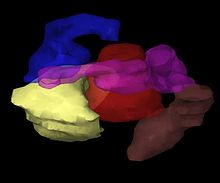

Body sites in which brachytherapy can be used to treat cancer.

Brachytherapy is commonly used to treat cancers of the cervix, prostate, breast, and skin.[1]

Brachytherapy can also be used in the treatment of tumours of the brain, eye, head and neck region (lip, floor of mouth, tongue, nasopharynx and oropharynx),[10] respiratory tract (trachea and bronchi), digestive tract (oesophagus, gall bladder, bile-ducts, rectum, anus),[11] urinary tract (bladder, urethra, penis), female reproductive tract (uterus, vagina, vulva), and soft tissues.[1]